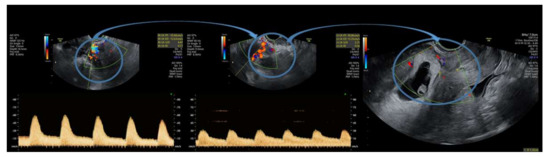

| P1 * | 99,999 | 7w + 1d | Type 1 | 1. Intramuscular methotrexate injection 2. Uterine artery embolization 3. Suction evacuation | No complications |

| P2 | 99,999 | 5w + 2d | Type 2 | 1. Intramuscular methotrexate injection 2. Uterine artery embolization 3. Suction evacuation | No complications |

| P3 | 62,309 | 7w + 2d | Type 2 | 1. Intramuscular methotrexate injection 2. Uterine artery embolization 3. Suction evacuation | No complications |

| P4 | 5938 | 5w + 5d | Type 1 | 1.Intramuscular methotrexate injection 2. Suction evacuation | No complications |

| P5 | 4579 | 5w + 6d | Type 2 | 1.Intramuscular methotrexate injection 2. Uterine artery embolization 3.Suction evacuation | No complications |

| P6 | 70,373 | 6w + 5d | Type 1 | 1. Intramuscular methotrexate injection 2. Uterine artery embolization 3. Suction evacuation | No complications |

| P7 | 46,317 | 6w + 2d | Type 2 | 1. Intramuscular methotrexate injection 2. Uterine artery embolization 3. Suction evacuation | No complications |

| P1 * | 2 | absent | increased | 11 | 22/20 | 27.5 |

| P2 | 2.1 | absent | increased | Not measured | 11 | 22.5 |

| P3 | 1.6 | present | increased | 13 | 24 | 28.4 |

| P4 | 3.3 | absent | normal | 2 | 8 | 33.6 |

| P5 | 4 | absent | normal | Not measured | 8 | 29.4 |

| P6 | 3.8 | absent | increased | 4 | 23 | 19.7 |

| P7 | 3.5 | present | increased | 5 | 28 | 21 |